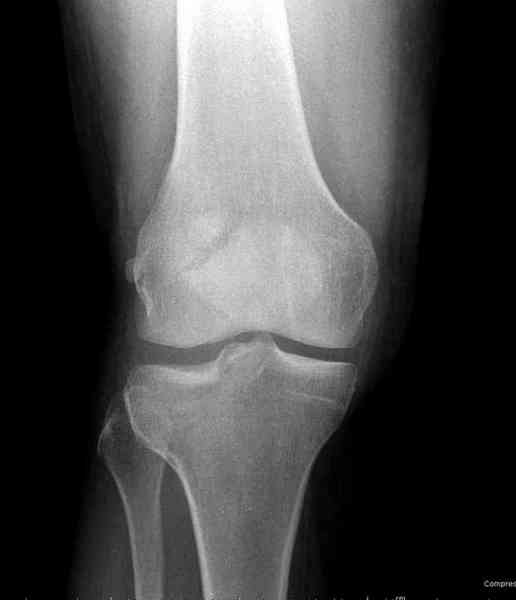

Около 60% переломов тибиал плато характеризуются мягкоткаными повреждениямм - разрывы суставной капсулы, связок и менисков. Мениск повреждается спереди со стороны перелома.

Тактику удаления мениска во время восстановления считаю ошибочной, наоборот, всеми путями надо его сохранить, потому что предупреждает от деформирующего артроза.

"Removal of a meniscus during the fracture surgery resulted in secondary degeneration in 74% of the cases. When a meniscus was intact or repaired, the proportion of degenerative cases was only 37%. Normal or slight valgus alignment of the tibial plateau with intact menisci protected best against secondary degeneration. On the other hand, medial or lateral tilt of the tibial plateau with a removed meniscus was followed by osteoarthritis in most cases. Honkonen SE., J Orthop Trauma. 1995"